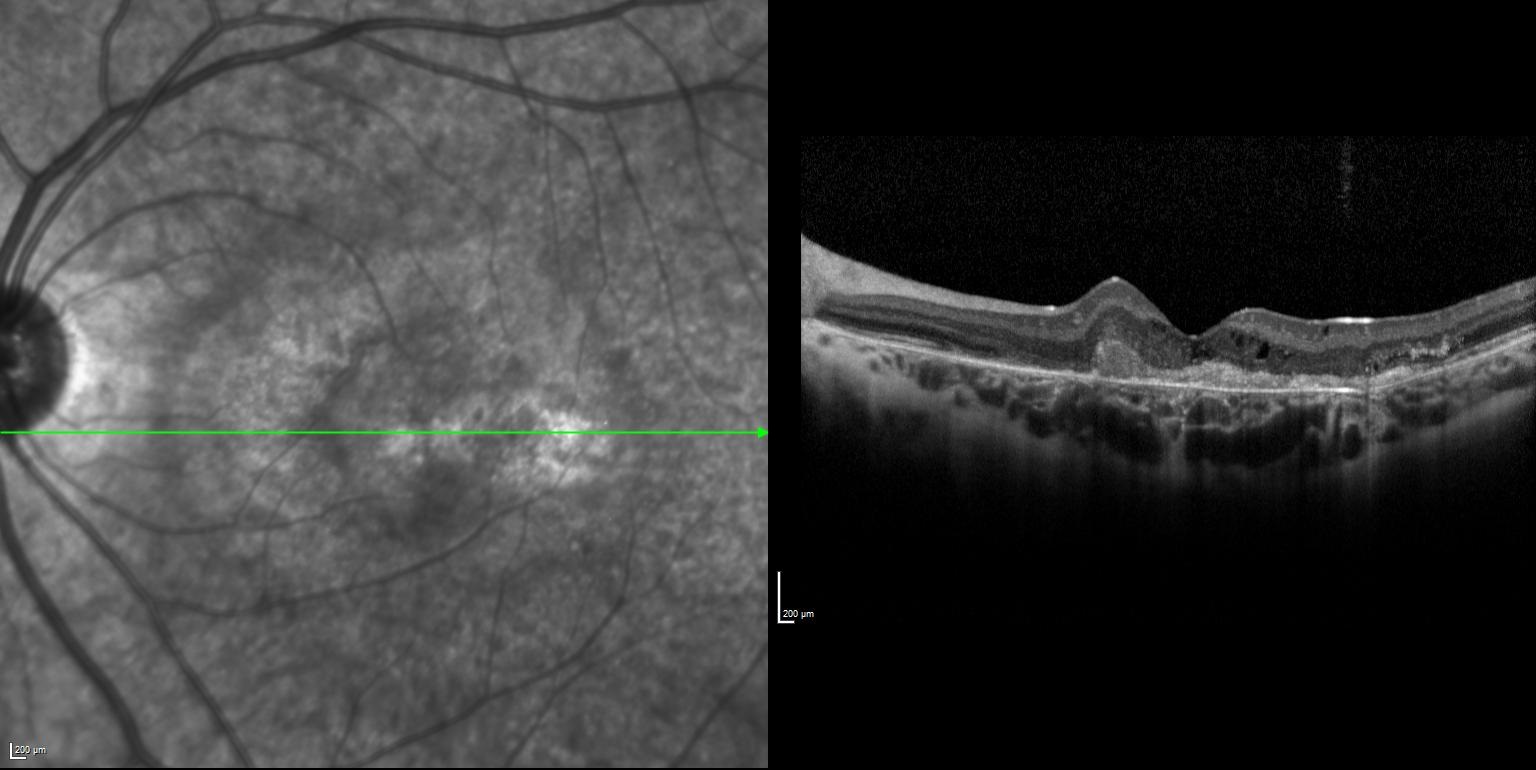

Sol gözde bir haftadır görme azlığı şikayeti başlayan ve görme keskinliği 5 mps düzeyinde olan 15 yaşındaki kadın hasta retina kliniğimize refere edilmiştir. Hastanın renkli fundus ve optik koherens tomografi görüntülerini görmektesiniz. Hastanın doğumunda bir enfeksiyon öyküsü vardır. Sistemik bir hastalığı yoktur. Bu bulgulara göre tanınız nedir? Lütfen cevabınızı aşağıya yazınız.